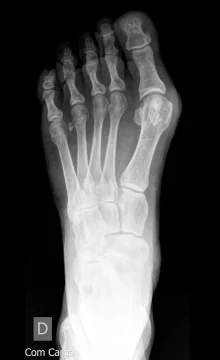

O joanete — chamado tecnicamente de hallux valgus — é um desvio progressivo do primeiro osso do pé que empurra o dedão em direção aos demais. Isso cria a saliência característica na lateral do pé, que vai se tornando cada vez mais dolorosa.

Não é toda pessoa com joanete que precisa de cirurgia. A decisão depende de uma avaliação individualizada, com exame clínico e radiográfico.